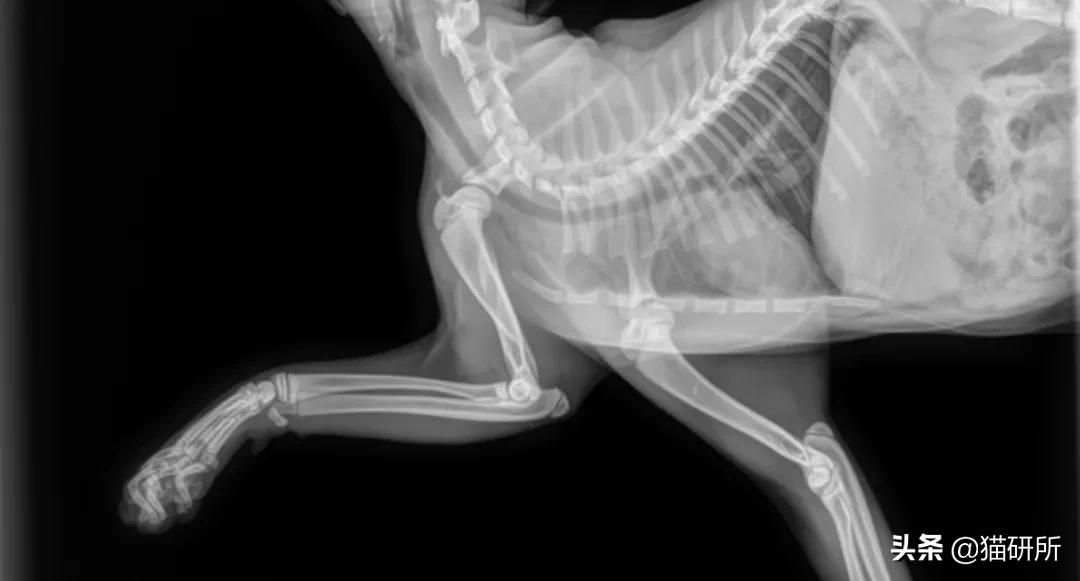

四肢骨骨折

最常见的骨折。绝大部分由外伤(不合理的运动,冲撞,跌倒等)导致。6个月以下或肥胖的猫更为常见。

猫四肢骨骨折 图自:猫研所动物医院